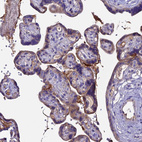

Immunohistochemical staining of human liver shows moderate cytoplasmic positivity in hepatocytes.